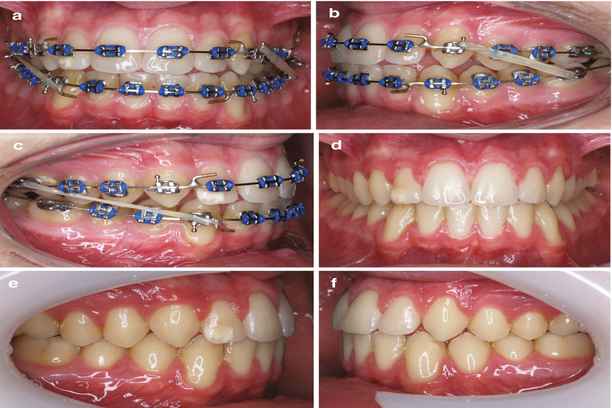

تعد صحة الفم والأسنان أكثر من مجرد مظهر جمالي، فهي تؤثر بشكل مباشر على وظيفة الفك وتوازن ملامح الوجه. من هنا يظهر دور فوائد تقويم الاسنان للوجه كعامل أساسي لا يقتصر على تنظيم الأسنان فحسب، بل يشمل تحسين التناسق الجمالي وتحقيق توازن عضلي وهيكلي للوجه.

يلجأ الكثيرون إلى التقويم ليس فقط لإصلاح مشاكل العض أو الأسنان المتراصة، بل أيضًا لتحسين الشكل العام للوجه، ورفع الثقة بالنفس. إن فهم فوائد تقويم الاسنان للوجه يتطلب معرفة عميقة بكيفية تأثير حركة الأسنان والفك على خطوط الوجه، حجم الفكين، وملامح الابتسامة الطبيعية.

التغييرات المحتملة في الوجه

خلال فترة التقويم، تحدث مجموعة من التغييرات التي تؤثر على ملامح الوجه:

- تعديل زاوية الفك السفلي والعلوي بما يعزز التوازن بين خطوط الوجه.

- شد العضلات الرخوة حول الفكين والخدين، مما يقلل من الترهل الطفيف ويعطي مظهرًا أكثر شبابًا.

- تصحيح الانسجام بين الأسنان الأمامية والخلفية ما يؤثر على الابتسامة ووضعية الشفاه.

- ضبط الفك العلوي في حالات البروز الشديد لتقليل المظهر العدواني أو الغير متوازن للوجه.

- إعادة توزيع الضغط على الأسنان الخلفية بما يقلل من الإرهاق العضلي ويؤثر على خطوط الفك الجانبية.

- تحسين الوضعية العامة للفك والرقبة بما يدعم الانحناءات الطبيعية للوجه.

شكل الوجه قبل وبعد التقويم

يعد التغيير في شكل الوجه قبل وبعد التقويم من أهم الملاحظات التي يراها المرضى:

- الوجه يبدو أكثر انسجامًا وتناسقًا بعد تعديل وضعية الفكين والأسنان.

- خطوط الفك السفلي تصبح أكثر تحديدًا ويقل بروز الفك العلوي أو السفلي في الحالات الشديدة.

- الابتسامة تصبح أكثر طبيعية ومتوازنة مع خطوط الوجه، مع تحسين شكل الشفاه والخدين.

- التوازن العضلي يقلل من التوتر والخطوط السطحية في الوجه ويعطي مظهرًا أكثر شبابًا.

- التغييرات الجمالية تدعم فوائد تقويم الاسنان للوجه بشكل واضح وملموس في كل مرحلة من مراحل العلاج.

ثانيًا: التغييرات في شكل الوجه من التقويم

أحد أبرز نتائج التقويم هي التغيرات المرئية في الوجه والتي تُظهر فوائد تقويم الاسنان للوجه بوضوح:

- تعديل وضعية الفك السفلي والعلوي لتحقيق توازن جانبي ووسطى للوجه.

- شد العضلات الرخوة حول الخدين والفك، مما يقلل من الترهل الطفيف ويعطي مظهرًا أكثر شبابًا.

- إعادة توزيع الضغط على الأسنان الخلفية يقلل من توتر العضلات، مما ينعكس على استرخاء خطوط الوجه.

- تعديل الشفاه والفم لتصبح الابتسامة أكثر طبيعية ومتناسقة مع بقية ملامح الوجه.

- التأثير الإيجابي على الأنف يكون واضحًا في بعض الحالات، حيث أن تعديل الفك العلوي السفلي قد يغير مظهر الانحناءات والزاوية بين الأنف والفك.

- تعزيز التناغم بين الأسنان والفك يحقق نتائج جمالية طويلة الأمد مع دعم الوظائف الحيوية للفم.